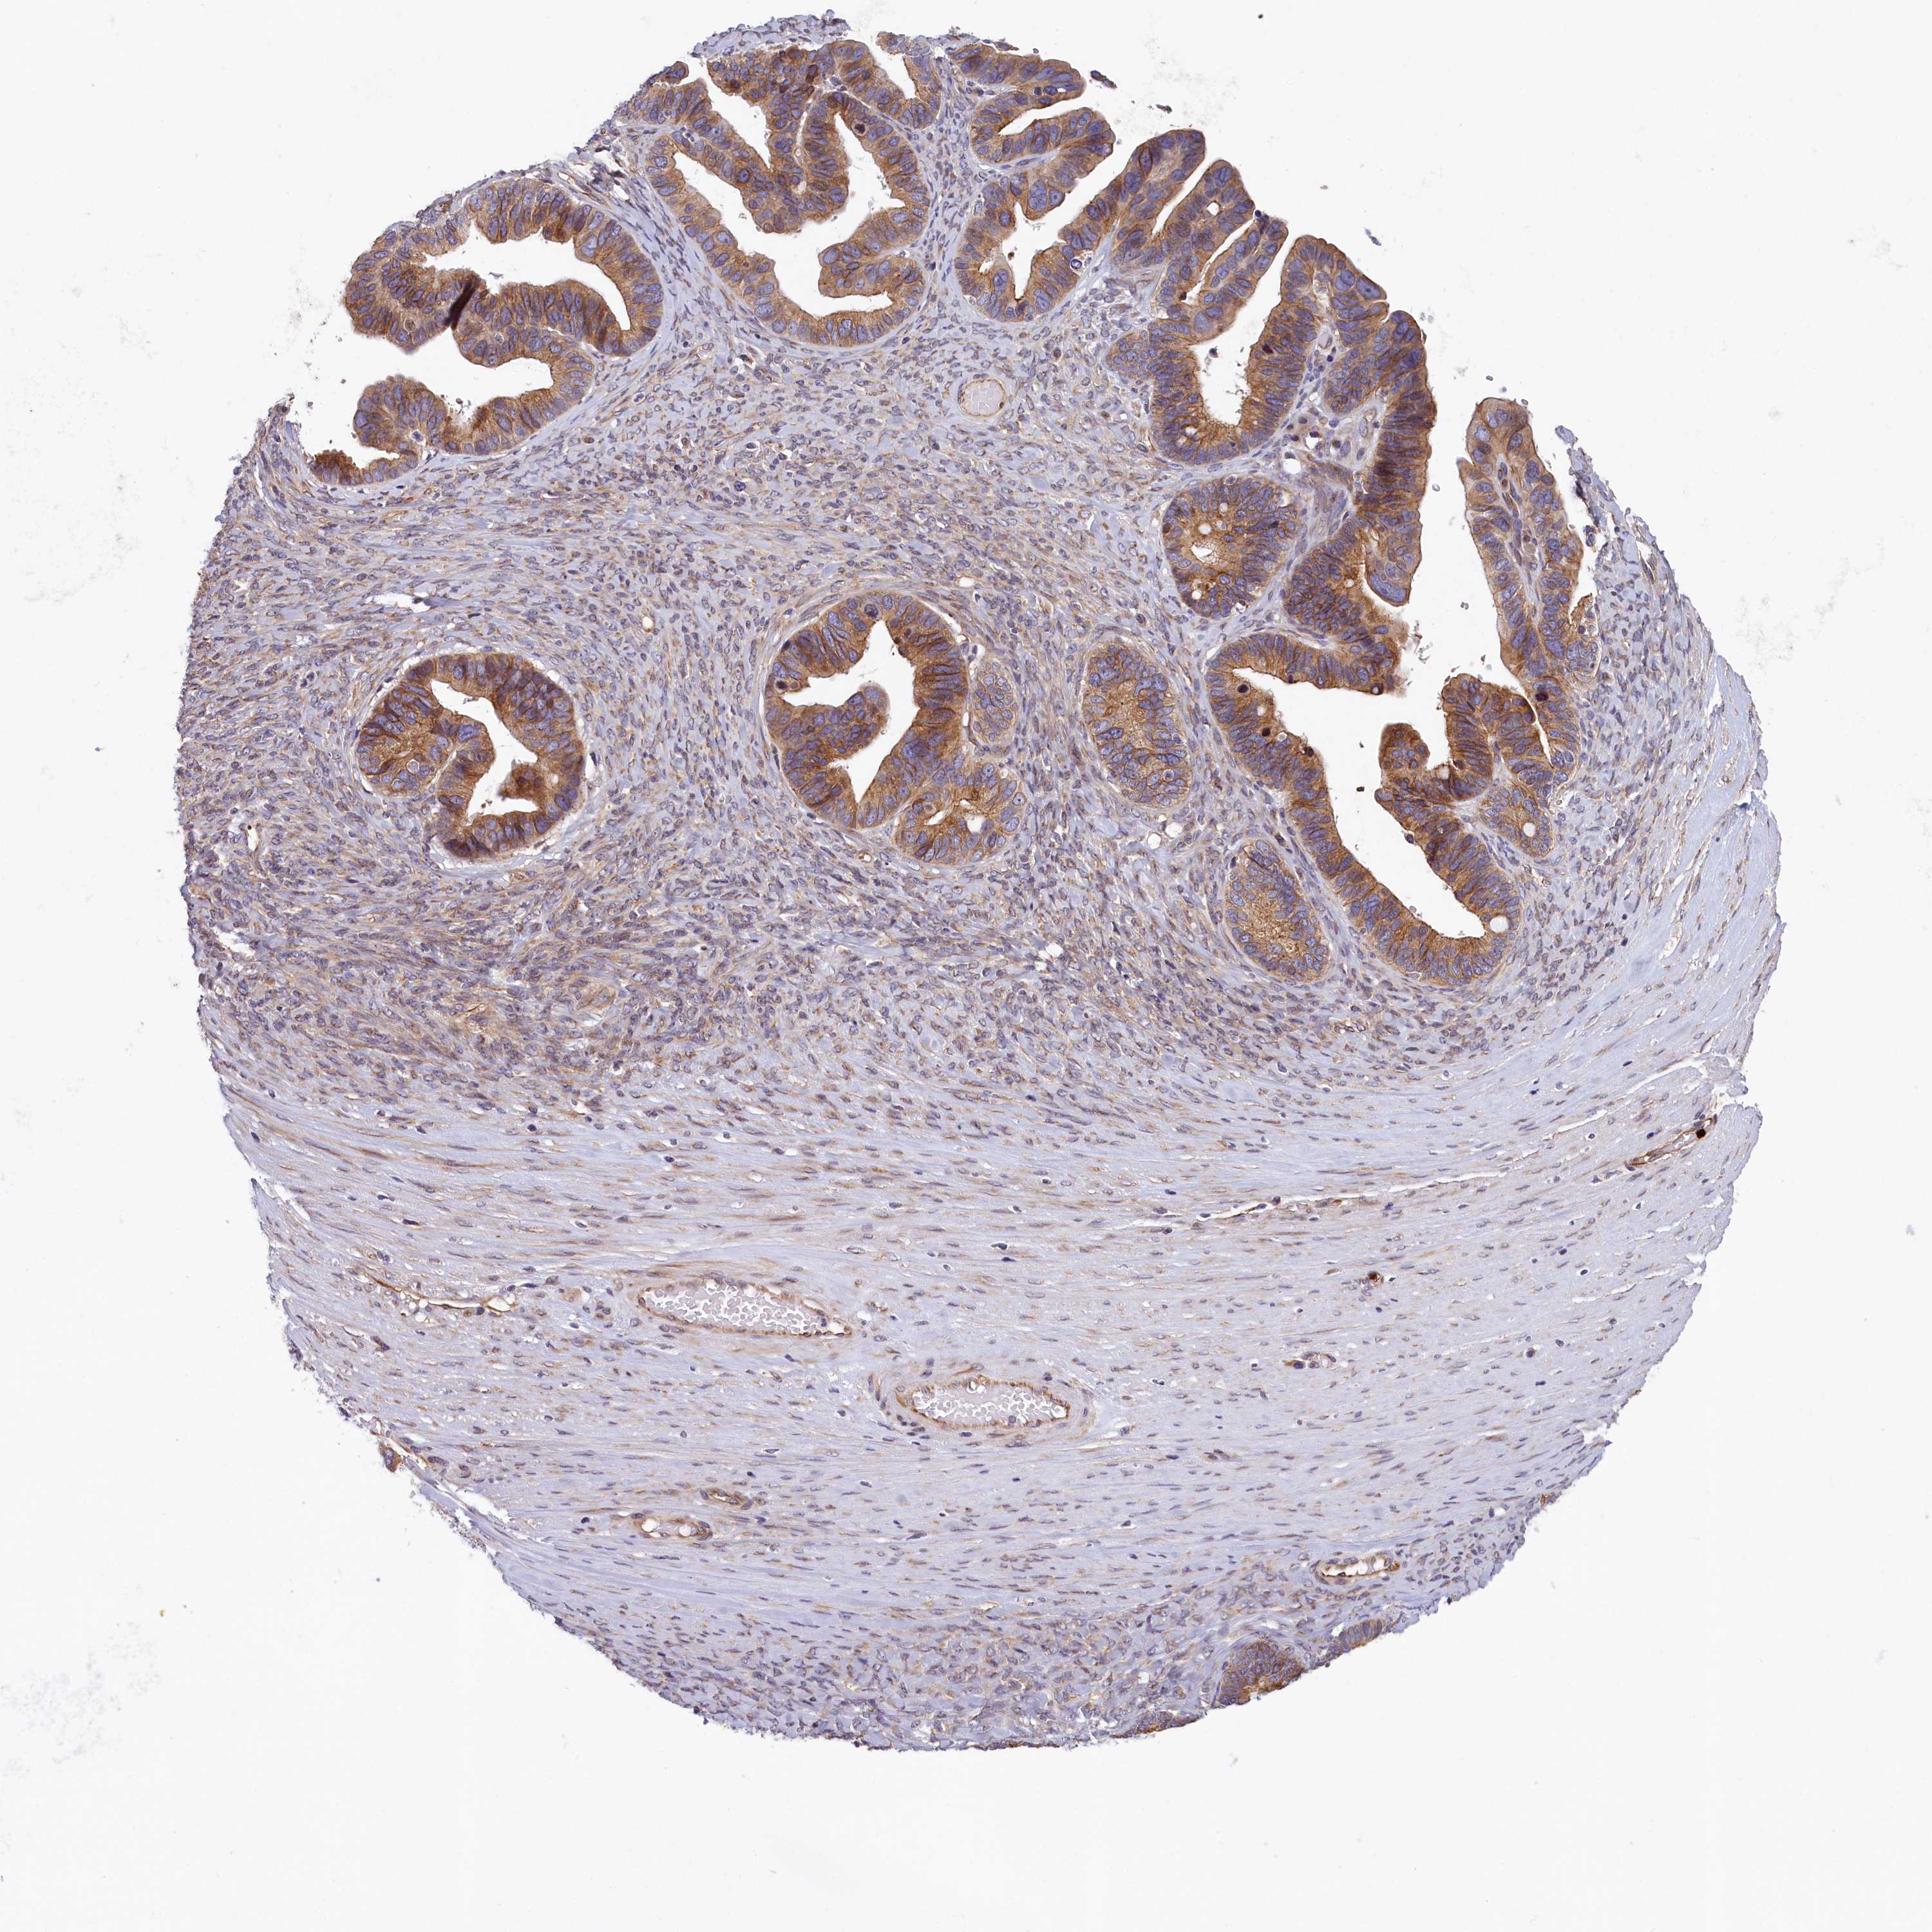

OVARIAN CANCER - Protein expressioni

A mouse-over function shows sample information and annotation data. Click on an image to view it in a full screen mode. Samples can be filtered based on level of antibody staining by selecting one or several of the following categories: high, medium, low and not detected. The assay and annotation is described here.

Note that samples used for immunohistochemistry by the Human Protein Atlas do not correspond to samples in the TCGA dataset.

Antibody stainingi

Antibody staining in the annotated cell types in the current human tissue is reported as not detected, low, medium, or high, based on conventional immunohistochemistry profiling in selected tissues. This score is based on the combination of the staining intensity and fraction of stained cells.

Each image is clickable and will lead to virtual microscopy that enables deeper exploration of all samples and also displays staining intensity scores, fraction scores and subcellular localization as well as patient and tissue information for each sample.

Antibody HPA040824

Staining

High

Medium

Low

Not detected

Intensity

Strong

Moderate

Weak

Negative

Quantity

>75%

75%-25%

<25%

None

Location

Nuclear

Cytoplasmic/membranous

Cytoplasmic/membranous,nuclear

Cystadenocarcinoma, serous, NOS

Carcinoma, endometroid

Cystadenocarcinoma, mucinous, NOS

Carcinoma, NOS